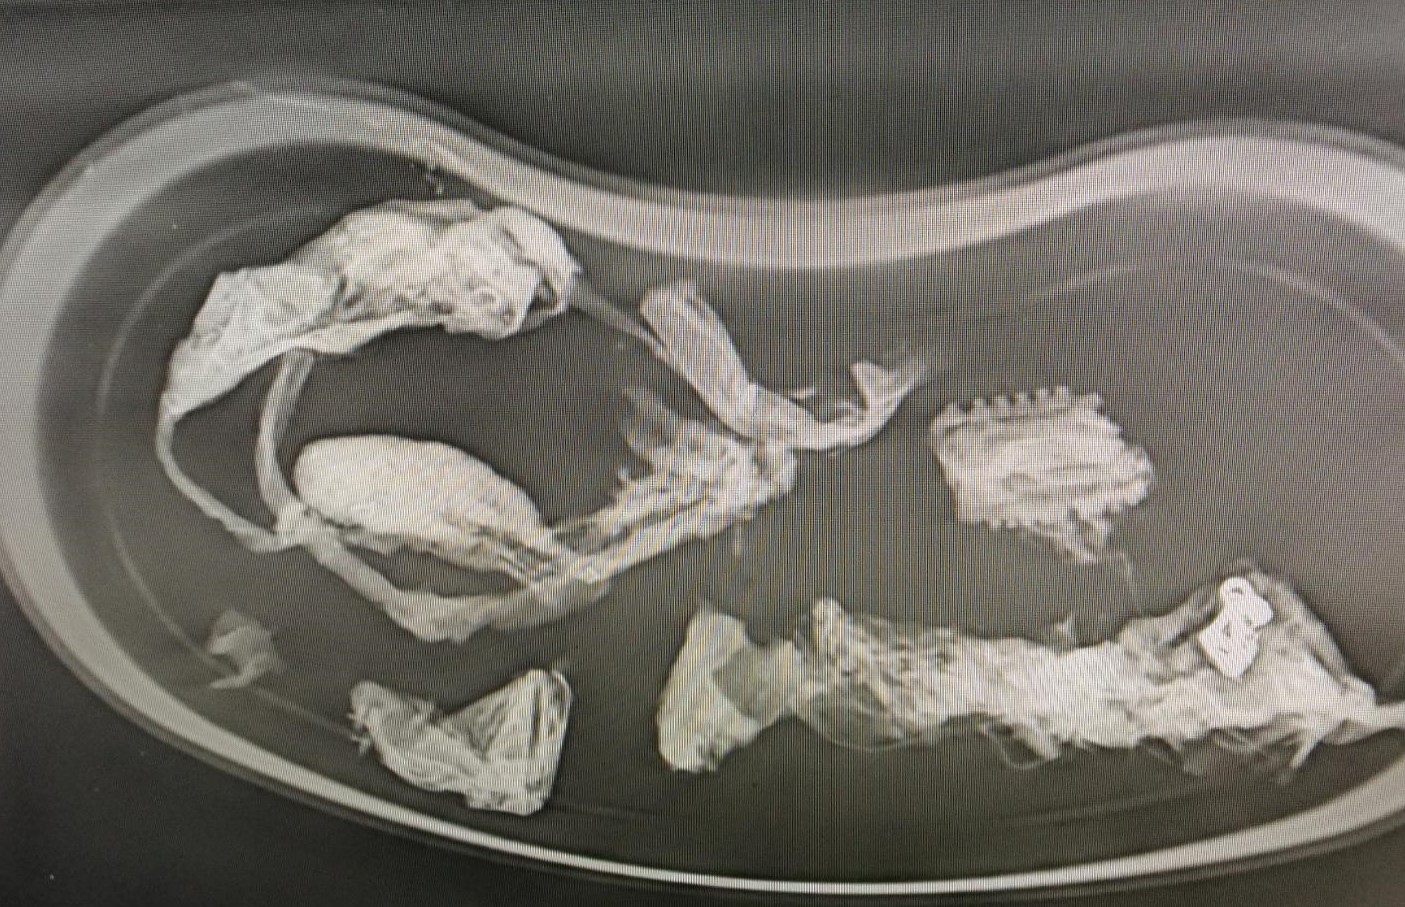

Lineární cizí těleso u 11měsíčního ridgebacka - z rozkousané bundy se zipem a plastového předmětu se vytvořilo lineární cizí těleso bezprostředně ohrožující život, které se na jednom konci zachytilo v žaludku a na druhý konec se navlékla cca 1/2 tenkého střeva. Za ní se bohužel vytvořila tzv invaginace - vchlípení jednoho úseku tenkého střeva do druhého. Kovový jezdec, který byl velmi dobře patrný na rentgenu, byl paradoxně volně v tlustém střevě a nezpůsoboval významnější obtíže. Museli jsme na několika místech vstoupit do žaludku a střev, přerušit a vyjmout cizí těleso, uvolnit vchlípení, zrevidovat životaschopnost střev a po zhodnocení stavu a perfuze krví uvést vše do původního stavu a dutinu břišní po výplachu uzavřít. Pacientovi se daří dobře, střeva fungují a už sám přijímá potravu.